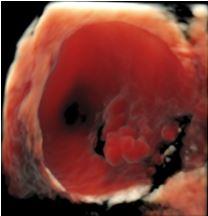

L’expertise dell’operatore, associato all’acquisizione da parte dell’Istituto di un’apparecchiatura di alto livello, dotata di software di ultima generazione anche con 3D e 4D, permettono di caratterizzare nei minimi dettagli l’eventuale presenza di patologia ovarica e di verificare l’eventuale disseminazione limitrofa agli organi circostanti. Questo da una parte dovrebbe permettere di evitare di misconoscere o sottovalutare alcune patologie ovariche potenzialmente evolutive in senso maligno e pertanto da indirizzare a trattamento chirurgico, e dall'altra di condurre un follow-up ecografico ad alcune patologie ovariche definite benigne secondo criteri standardizzati e ampiamente validati atti ad evitare una chirurgia non necessaria. Nel gruppo di lavoro IOTA infatti si è visto in questi anni che quasi l'80 percento delle masse ovariche operate risultavano benigne. E’noto che ogni procedura chirurgica è associata a possibili complicanze a breve come a lungo termine.